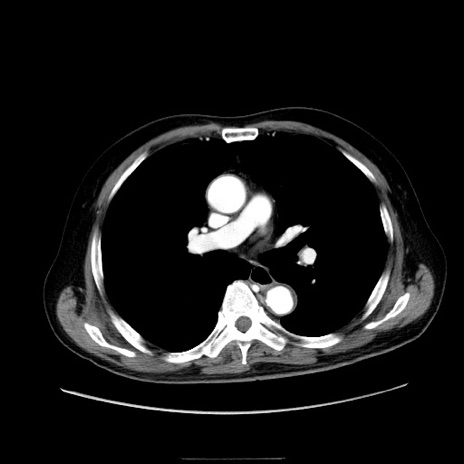

症例30(横断像)

【症例】80歳代男性

【主訴】臍周囲痛

【現病歴】約6時間前から臍下部痛が出現。次第に腹部膨隆・背部痛も生じてきたため来院。背部痛の場所は変化しない。

【身体所見】意識清明、BT 36.3℃、BP  131/87mmHg、P 87bpm、SpO2 100%(RA)、臍周囲自発痛・圧痛あり、反跳痛なし、自発痛部位に一致して板状硬あり、腹部膨隆、腸雑音減弱、CVA tenderness両側陰性。

【データ】WBC 19600、CRP 0.33